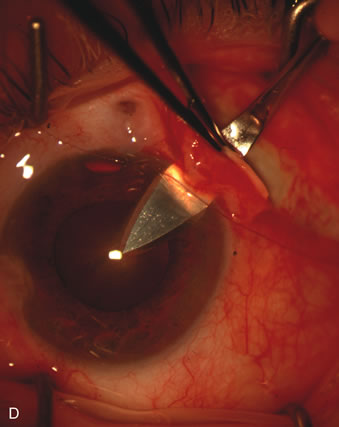

The inflammation associated with lens extraction at any site usually causes complete failure of a marginal functioning bleb. In addition, pressure reduction by medical means is usually minimal in these recalcitrant cases, and combined surgery is indicated. In the past, these cases were approached with large-incision ECCE, clear corneal cataract incision, and bleb revision. Drawbacks included those mentioned earlier for large incision clear corneal cataract extraction, and bleb revision is often associated with conjunctival buttonholes, wound leaks, subconjunctival hematoma, destruction of friable sclera, and associated hypotony. With the advent of modern-day cataract surgery, a phacotrabeculectomy is often possible adjacent to the failed filter (Fig. 7). The ability to combine cataract extraction with implant and filtration surgery all through the same small incision has greatly improved outcomes for patients with marginal preoperative filters. There are several other viable options in this case. If the surgeon elects to remove the cataract through a temporal clear corneal incision, the bleb may be revised or a new adjacent filter fashioned. As mentioned earlier, revising a failed filter is technically challenging. If the surgeon believes it is not feasible to revise the filter or fashion a new one, a glaucoma drainage implant is a reasonable option combined with temporal lens extraction.172

Fig. 7. Phacotrabeculectomy adjacent to a failed filter in cataractous eye. The ability to combine small-incision cataract extraction with trabeculectomy all through the same incision adjacent to the failed filter allows the surgeon to work in a familiar superior area. Avoiding incisions into the existing bleb decreases conjunctival buttonholes, hypotony, operating room time, and subconjunctival bleeding. A. Appearance of failed bleb with exposure of superior temporal quadrant gained with a corneal traction suture. B. Prepare a limbus-based conjunctival flap and a scleral flap. C. This bleb is at high risk to fail again justifying the need for MMC, 0.2 mg/cc applied on a pledget for 4 minutes. D. Insert the keratome and perform phacotrabeculectomy in the usual fashion.